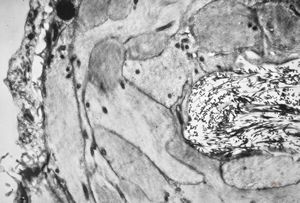

rabbit spinal cord trauma